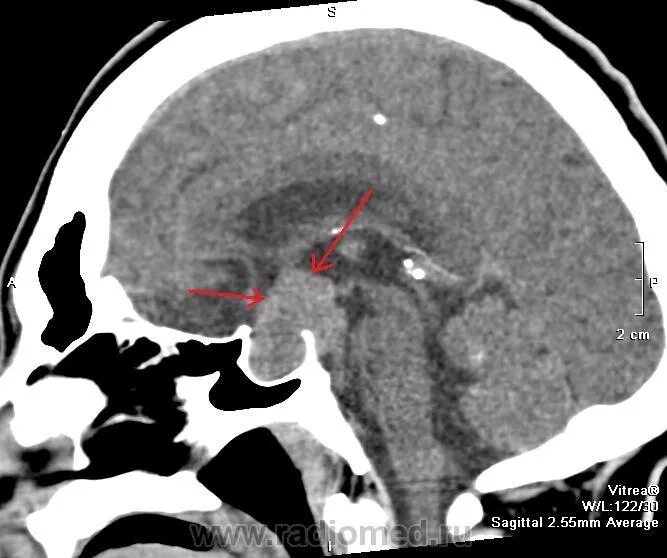

Спинка турецкого седла